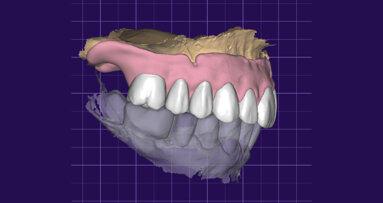

Il piano di trattamento prevede l’estrazione degli elementi dentali, l’inserimento di due impianti e la realizzazione di una protesi fissa di quattro elementi. Il problema da gestire è quello della fase provvisoria. Non è ipotizzabile una protesi mobile e quindi programmiamo di inserire subito dopo l’intervento un provvisorio immediato. Questo ci consente di condizionare da subito i tessuti periimplantari e anche le zone dei ponti. Si rileva un’impronta digitale (Figg. 5, 6), e la programmazione degli impianti viene effettuata con un software di chirurgia guidata (Fig. 7) e la posizione degli impianti nello spazio biologico e nello spazio protesico viene fatta sulla base di una ceratura diagnostica (Figg. 8, 9). Inseriamo gli impianti virtuali nell’osso disponibile (Figg. 10-13) e in relazione all’aspetto protesico correggiamo l’asse di inclinazione degli impianti con componenti secondarie angolate a 17° (Figg. 14, 15). Questo ci consentirà di realizzare una protesi avvitata con i fori situati nella zona palatale.

Fig. 7 - Sovrapposizione del File PLY della ceratura e dei tessuti.

Il nostro obiettivo è quello di riuscire a dare alla paziente un provvisorio immediato nell’arco di due ore. Questo diventa possibile perché abbiamo utilizzato un flusso digitale fin dall’inizio. In laboratorio vengono realizzate la dima chirurgica (Figg. 16, 17), la dima protesica (Fig. 18) e anche il provvisorio (Figg. 19-21) che contiene delle alette di riposizionamento. Il tutto gestito con modelli digitali sui quali saremo in grado di funzionalizzare il provvisorio post-chirurgico (tecnica DIL). In un caso come questo se utilizziamo un flusso digitale possiamo evitare subito dopo la chirurgia di rilevare un’impronta degli impianti inseriti. Infatti, utilizziamo una dima chirurgica che ci faciliterà le fasi di intervento. La dima ci consentirà di non fare lembi e nessuna incisione di rilascio (Fig. 22), dopo aver inserito gli impianti (BLX Straumann) (Figg. 23-31) e aver controllato il loro alloggiamento, inseriamo sugli stessi dei transfert da impronta (Fig. 32).

Fig. 19 - Modelli digitali relazionati.

Fig. 20 - Modello master di lavoro.

Fig. 21 - Modello Master e provvisorio pre-chirurgico.

Alloggiamo la dima protesica (Fig. 33), e blocchiamo i transfert con della resina trasparente (tecnica DIL) (Figg. 34, 35). In questo modo possiamo far riposare il paziente in studio dopo appena 35 minuti dall’inizio dell’intervento. La dima protesica, infatti (Fig. 36) con i transfert inseriti viene completata con l’unione degli analoghi ai transfert (Fig. 37). L’insieme così composto viene riadattato sul modello master digitale iniziale (Figg. 38-40) sul quale era stata costruita sia la dima chirurgica che la dima protesica come anche il provvisorio. Gli analoghi vengono bloccati sul modello con resina trasparente (Figg. 41-43). Alloggiamo il provvisorio sul modello master digitale così ottenuto (Figg. 44, 45).

Il risultato sarà quello di ottenere un modello master già relazionato all’arcata antagonista e soprattutto un modello che contiene la posizione esatta degli impianti appena inseriti. Questo rappresenta il cuore della tecnica DIL, evitiamo impronta post-chirurgica, evitiamo la registrazione di una nuova dimensione verticale e realizziamo il modello di lavoro in pochissimo tempo.

Le fasi successive sono tecniche, uniamo la componente secondaria angolata a 17° programmata agli analoghi degli impianti (Figg. 46-49), su di essa avviteremo il moncone SRA (Figg. 50, 51). Alloggeremo il provvisorio sul modello (Fig. 52) e le alette di riposizionamento ci consentiranno di essere precisi. Unire il provvisorio alle componenti secondarie sarà a questo punto molto semplice con resina fotopolimerizzabile (Fig. 53). In poco più di un’ora abbiamo funzionalizzato il provvisorio (Figg. 54-57). Il montaggio del provvisorio avverrà collegando prima le componenti secondarie angolate agli impianti (Figg. 58, 59) e poi il provvisorio stesso (Figg. 60-70).